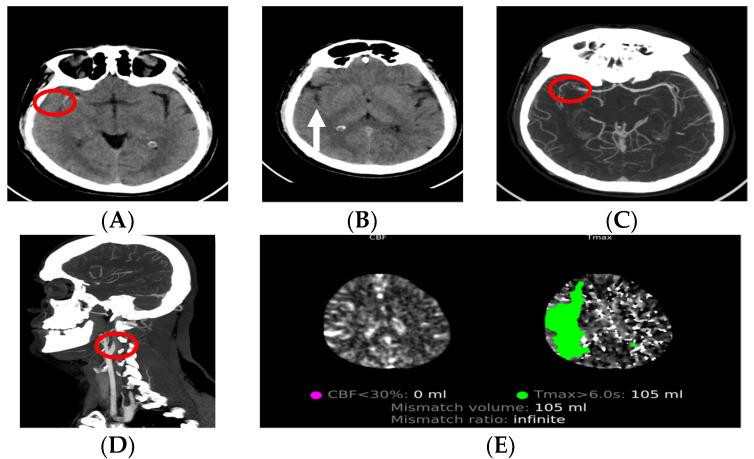

Neuroimaging Modalities Used for Ischemic Stroke Diagnosis and Monitoring.

Strokes are one of the global leading causes of physical or mental impairment and fatality, classified into hemorrhagic and ischemic strokes. Ischemic strokes happen when a thrombus blocks or plugs an artery and interrupts or reduces blood supply to the brain tissue. Deciding on the imaging modality which will be used for stroke detection depends on the expertise and availability of staff and the infrastructure of hospitals. Magnetic resonance imaging provides valuable information, and its sensitivity for smaller infarcts is greater, while computed tomography is more extensively used, since it can promptly exclude acute cerebral hemorrhages and is more favorable speed-wise. The aim of this article was to give information about the neuroimaging modalities used for the diagnosis and monitoring of ischemic strokes. We reviewed the available literature and presented the use of computed tomography, CT angiography, CT perfusion, magnetic resonance imaging, MR angiography and MR perfusion for the detection of ischemic strokes and their monitoring in different phases of stroke development.